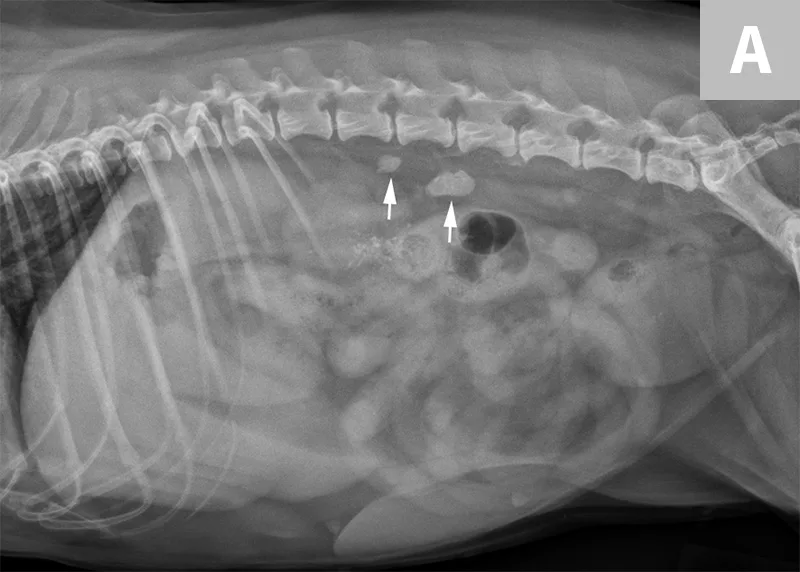

FIGURE 5A

Lateral abdominal radiograph of a dog with 2 well-defined, oval mineral opacities superimposed over the retroperitoneal space caudal and dorsal to the kidneys (arrows). Based on the ventrodorsal projection (not shown), these calculi were likely to be associated with the right ureter.